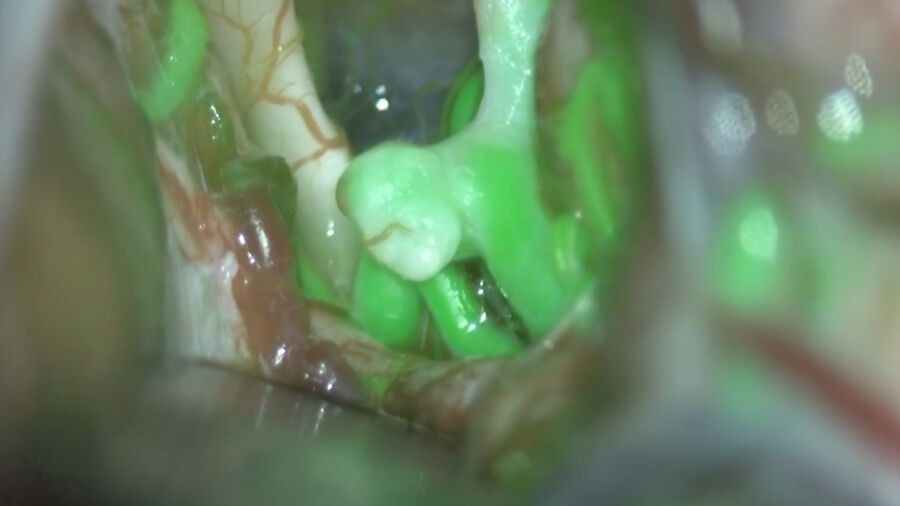

Augmented Reality fluorescence supports each step of neurovascular surgery procedures. Image courtesy of Dr. Christof Renner. Augmented_Reality_fluorescence_supports_neurovascular_surgery_procedures.jpg

Renner博士介绍,由于采用GLOW800增强现实荧光技术,可以在神经血管手术过程中直接在显微镜下看到血管造影图像,并获得最佳的深度感知。无需回忆和拼接黑白血流视频与自然解剖视图。

因此,GLOW800可以实时提供动脉期和静脉期的血液循环和灌注信息。这些信息可以帮助选择最安全的治疗方法和策略。也有助于验证病灶是否有效和明确消除。